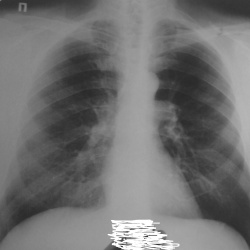

Мальчик 7лет 7 месяцев. в возрасте 5 лет поставлен диагноз нефробластома левой почки 4 стадии с мст легких, гистологически смешанный вариант...